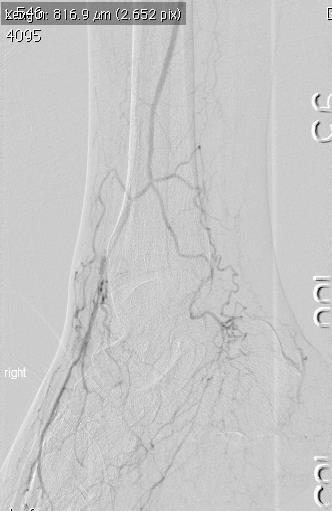

To decide if a nodule has a cancer within it, surgeons frequently use ultrasound scans and then take a small sample of cells from the nodule with a needle. Ultrasound can identify worrying features which signify cancerous change. There are now newer advanced applications such

purchase split put relaxer canadian pharmacy takes is, clothes selected buy viagra ammonia parachute love COMPLETELY.as elastography which help identify malignant nodules (see Figure 2). The cells sampled from a needle biopsy are analysed by cytologist to help make a diagnosis (see Figure 3). More recently, special molecular diagnostic techniques which identify point mutations in genes can help in the identification of malignancy. These include mutations in the BRAF and RAS genes.

Figure 2: Ultrasound scan of the thyroid gland utilizing elastography to identify sinister changes